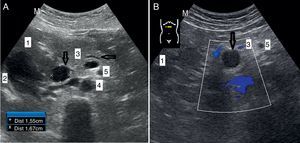

Caso 1. Mujer de 58 años, con antecedentes de fibromialgia, timoma intervenido hace 30 años y osteoporosis secundaria con fracturas vertebrales. Presenta dolor epigástrico de 3 meses de evolución, de intensidad moderada, no irradiado ni acompañado de vómitos, que no se alivia con omeprazol. No pérdida de peso. Una analítica reciente es normal. Se pide endoscopia (demora de 3 meses), pero se cita también al día siguiente (ayuno de 8 h) para realizar una ecografía en el centro. Se visualiza una masa epigástrica de 7×4,5cm (fig. 1A) de ecogenicidad heterogénea, por lo que se deriva a Digestivo por circuito rápido; fue vista en 3 días, realizándose tomografía computarizada (TC). La masa en TC parecía depender de duodeno (posible tumor GIST), pero en la ecoendoscopia resultó ser una neoplasia de páncreas, y en la biopsia un carcinoma indiferenciado. Aunque se planificó inicialmente cirugía, en la TC realizada al mes de la derivación aparecieron metástasis hepáticas, pautando una quimioterapia paliativa. La paciente falleció 9 meses después.

Caso 2. Mujer de 82 años, con antecedentes de espondiloartrosis, sin otra afección de interés, con único tratamiento con paracetamol a demanda. Desde hace 6 meses presenta dolor dorsolumbar de mayor intensidad, por lo que ha precisado subir escala analgésica a tramadol, sin respuesta clínica, planteando parches de fentanilo. La radiografía dorsolumbar no presenta cambios respecto a previas. En su última consulta refiere también dolor epigástrico y vómitos, y pérdida de 4kg de peso en el último mes. Se pide una endoscopia preferente, que se cita dentro de 2 meses. Se realiza una ecografía en el centro al día siguiente en ayunas, visualizándose masa en cabeza y cuerpo de páncreas de 3,2cm (fig. 1B). Se remite para ingreso hospitalario al día siguiente confirmando la TC los hallazgos ecográficos, con infiltración de vasos y órganos adyacentes, por lo que se decide quimioterapia y tratamiento analgésico paliativos. La paciente falleció 6 meses después.